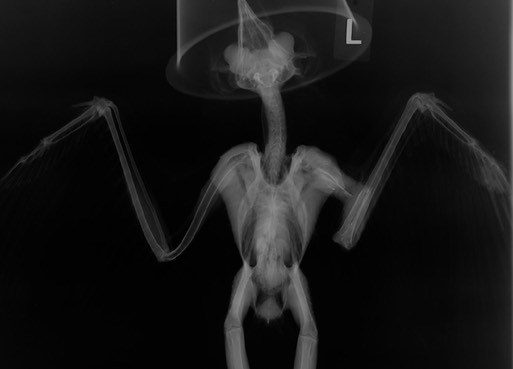

Barn Owl 19-107

An injured Barn Owl was found in the front yard of a home on Main Street in Ione. The owl had a brood patch (a bare patch on the abdomen that allows a bird to brood eggs) and a fractured humerus. A radiograph showed the owl had been shot. Initially, we thought the owl was a female because of the brood patch. A necropsy showed it was a male. This is the second male Barn Owl we’ve admitted with a brood patch. I used to think that only female Barn Owls incubated eggs. Apparently that is not the case. Hopefully the owl’s young are far enough along, and prey is abundant enough that the female can raise her brood on her own.